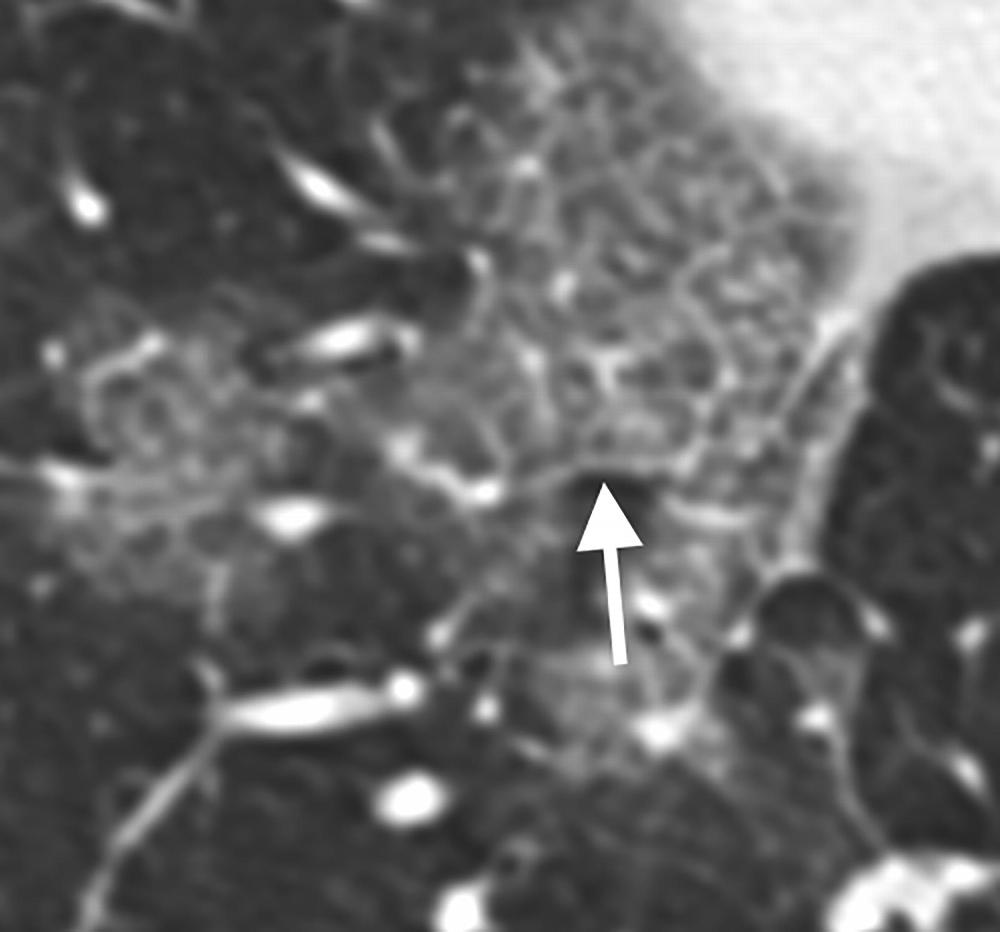

Figure 3. 66-year old female with history of recent travel to Wuhan, presenting with fever and productive cough. Axial thin-section coned-down non-contrast CT image shows a “crazy paving” pattern as manifested by right lower lobe ground-glass opacification and interlobular septal thickening (arrow) with intralobular lines.